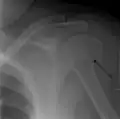

Diagnosis

Definitive diagnosis of humerus fractures is typically made through radiographic imaging. For proximal fractures, X-rays can be taken from a scapular anteroposterior (AP) view, which takes an image of the front of the shoulder region from an angle, a scapular Y view, which takes an image of the back of the shoulder region from an angle, and an axillar lateral view, which has the patient lie on his or her back, lift the bottom half of the arm up to the side, and have an image taken of the axilla region underneath the shoulder.[9] Fractures of the humerus shaft are usually correctly identified with radiographic images taken from the AP and lateral viewpoints.[12] Damage to the radial nerve from a shaft fracture can be identified by an inability to bend the hand backwards or by decreased sensation in the back of the hand.[5] Images of the distal region are often of poor quality due to the patient being unable to extend the elbow because of pain. If a severe distal fracture is suspected, then a computed tomography (CT) scan can provide greater detail of the fracture. Nondisplaced distal fractures may not be directly visible; they may only be visible due to fat being displaced because of internal bleeding in the elbow.[7]